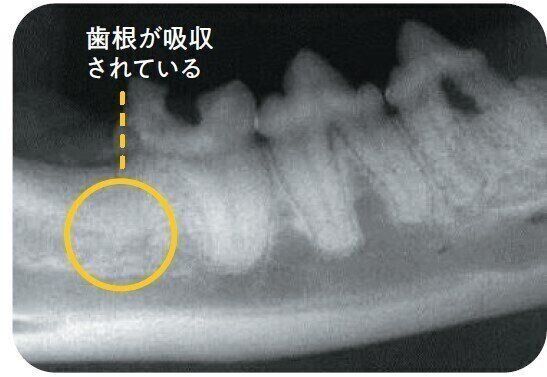

歯の吸収病巣タイプ2

歯冠も歯根も溶け、骨組織に吸収されるタイプ。中央の歯の歯根の輪郭が確認できますが、右の歯の歯根は溶けて輪郭がなくなっており、骨組織に置き換わっています。